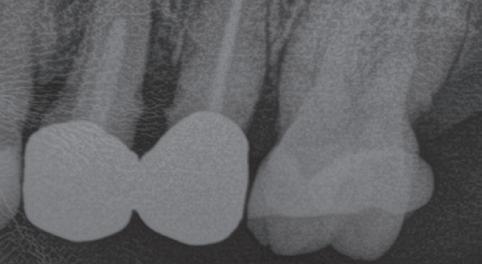

The standardisation of treatment procedures has resulted in less emphasis on craftmanship. I have quite a few gold restorations in my own mouth, two of which were placed there by a very fine dentist in 1968, both are still intact with no breakdown around the margins and both the teeth are functioning well, despite one of them having been root treated with silver points at the time. I take regular radiographs and there are absolutely no problems. I placed a number of gold restorations in my wife’s mouth before we were married in 1973 and they, too, are all still functioning well. And yet my laboratory, which

employs more than 30 technicians, has only one person who is still capable of producing good metal margins and despite all the emphasis on digital restorations and aesthetics, the dentists that I treat as patients prefer gold in their own mouths and for their families wherever possible.